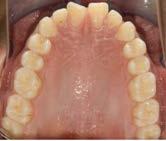

En la fotografía lateral derecha (Figura 4), de frente e izquierda se ve la clase II canina y molar bilateral, curva de Spee acentuada y laterales microdónticos. La línea media dental inferior está desviada a la izquierda 2 mm. En las oclusales superior e inferior, el apiñamiento leve superior e infierior, laterales superiores

microdónticos y formas de arco cuadradas (Figura 5).

Figura 5. Oclusal superior e inferior.